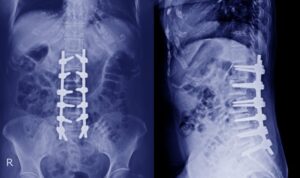

Advancements in medical technology have revolutionized the field of spine surgery. One of the most significant innovations is robotic spine surgery, which is quickly becoming the future of precision healthcare.…

In recent years, Minimally Invasive Spine Surgery in Bangalore has revolutionized the way spinal conditions are treated. For patients struggling with chronic back pain, herniated discs, spinal stenosis, or degenerative…

The spine is a crucial part of the human body, providing support, flexibility, and protection for the spinal cord. However, due to factors like poor posture, aging, or injuries, spine…